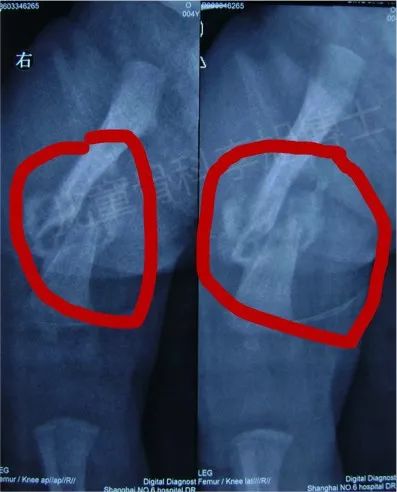

我们先来看看孩子出生第二天时拍的片子:

从片子上看,可以很明显地看到孩子右侧股骨骨折完全错位